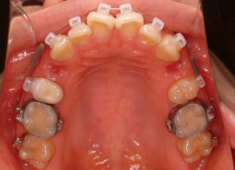

治療開始時

治療開始から1年7ヶ月後